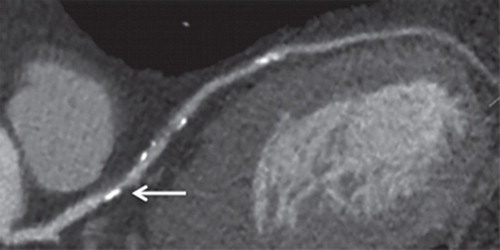

Tratamiento a valores objetivo o de alta intensidad con estatinas en pacientes con enfermedad de las arterias coronarias

08 marzo 2023

En este ensayo clínico aleatorizado, entre los pacientes con enfermedad de las arterias coronarias, una estrategia de LDL-C de 50 a 70 mg/dL como meta no fue inferior a un tratamiento de alta intensidad con estatinas para el desenlace compuesto de 3 años de muerte, infarto de miocardio , accidente cerebrovascular o revascularización coronaria. Estos hallazgos brindan evidencia adicional que respalda la idoneidad de una estrategia de tratamiento con cifras objetivo que puede permitir un enfoque personalizado teniendo en cuenta la variabilidad individual en la respuesta farmacológica a la terapia con estatinas. JAMA.  6 de marzo de 2023.